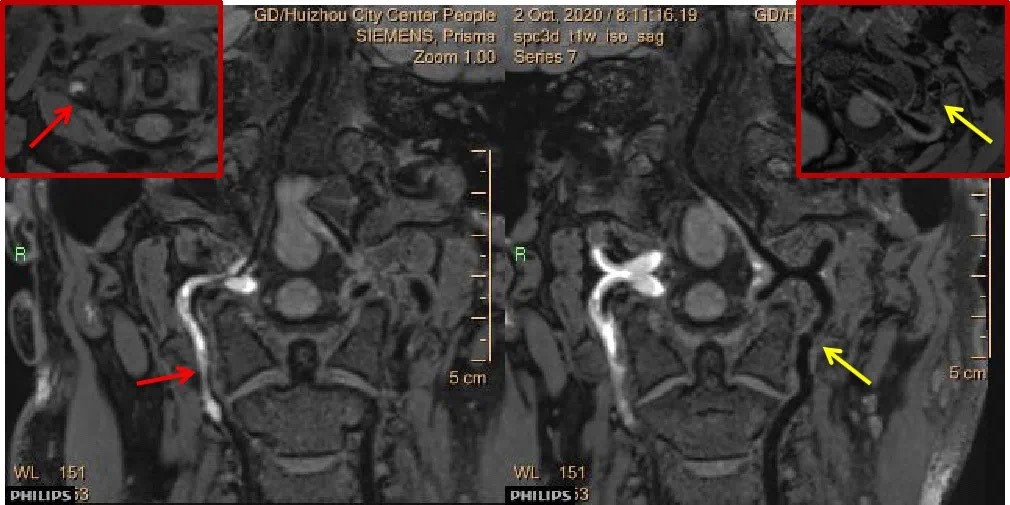

高分辨率磁共振血管壁成像技术具体“高”在哪里?在这项积水的帮助下,检查发现该女性右椎动脉V2-4段广泛内膜下血肿压迫血管真腔变窄,并不是先天发育不良。左椎动脉V3段内膜撕裂形成真假腔(CTA显示瘤样扩张改变),左V2-4段形成广泛内膜下血肿,压迫血管真腔狭窄不一。

追溯患者病史,该院医生发现患者病发前曾有颈部按摩治疗病史,结合血管壁成像考虑是双椎动脉夹层形成内膜下血肿导致的缺血性脑梗死。这下对症治疗就容易多了。